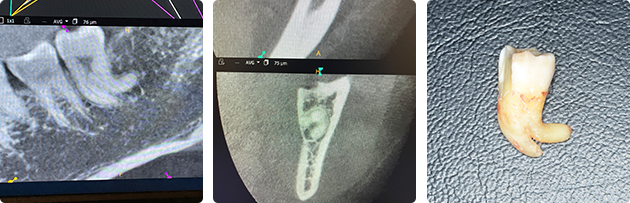

彎曲している親知らずの抜歯

親知らずの根が極端に彎曲し、下歯槽菅(下歯槽神経)に近接していました。根の破折なく抜歯を行い合併症も認めませんでした。